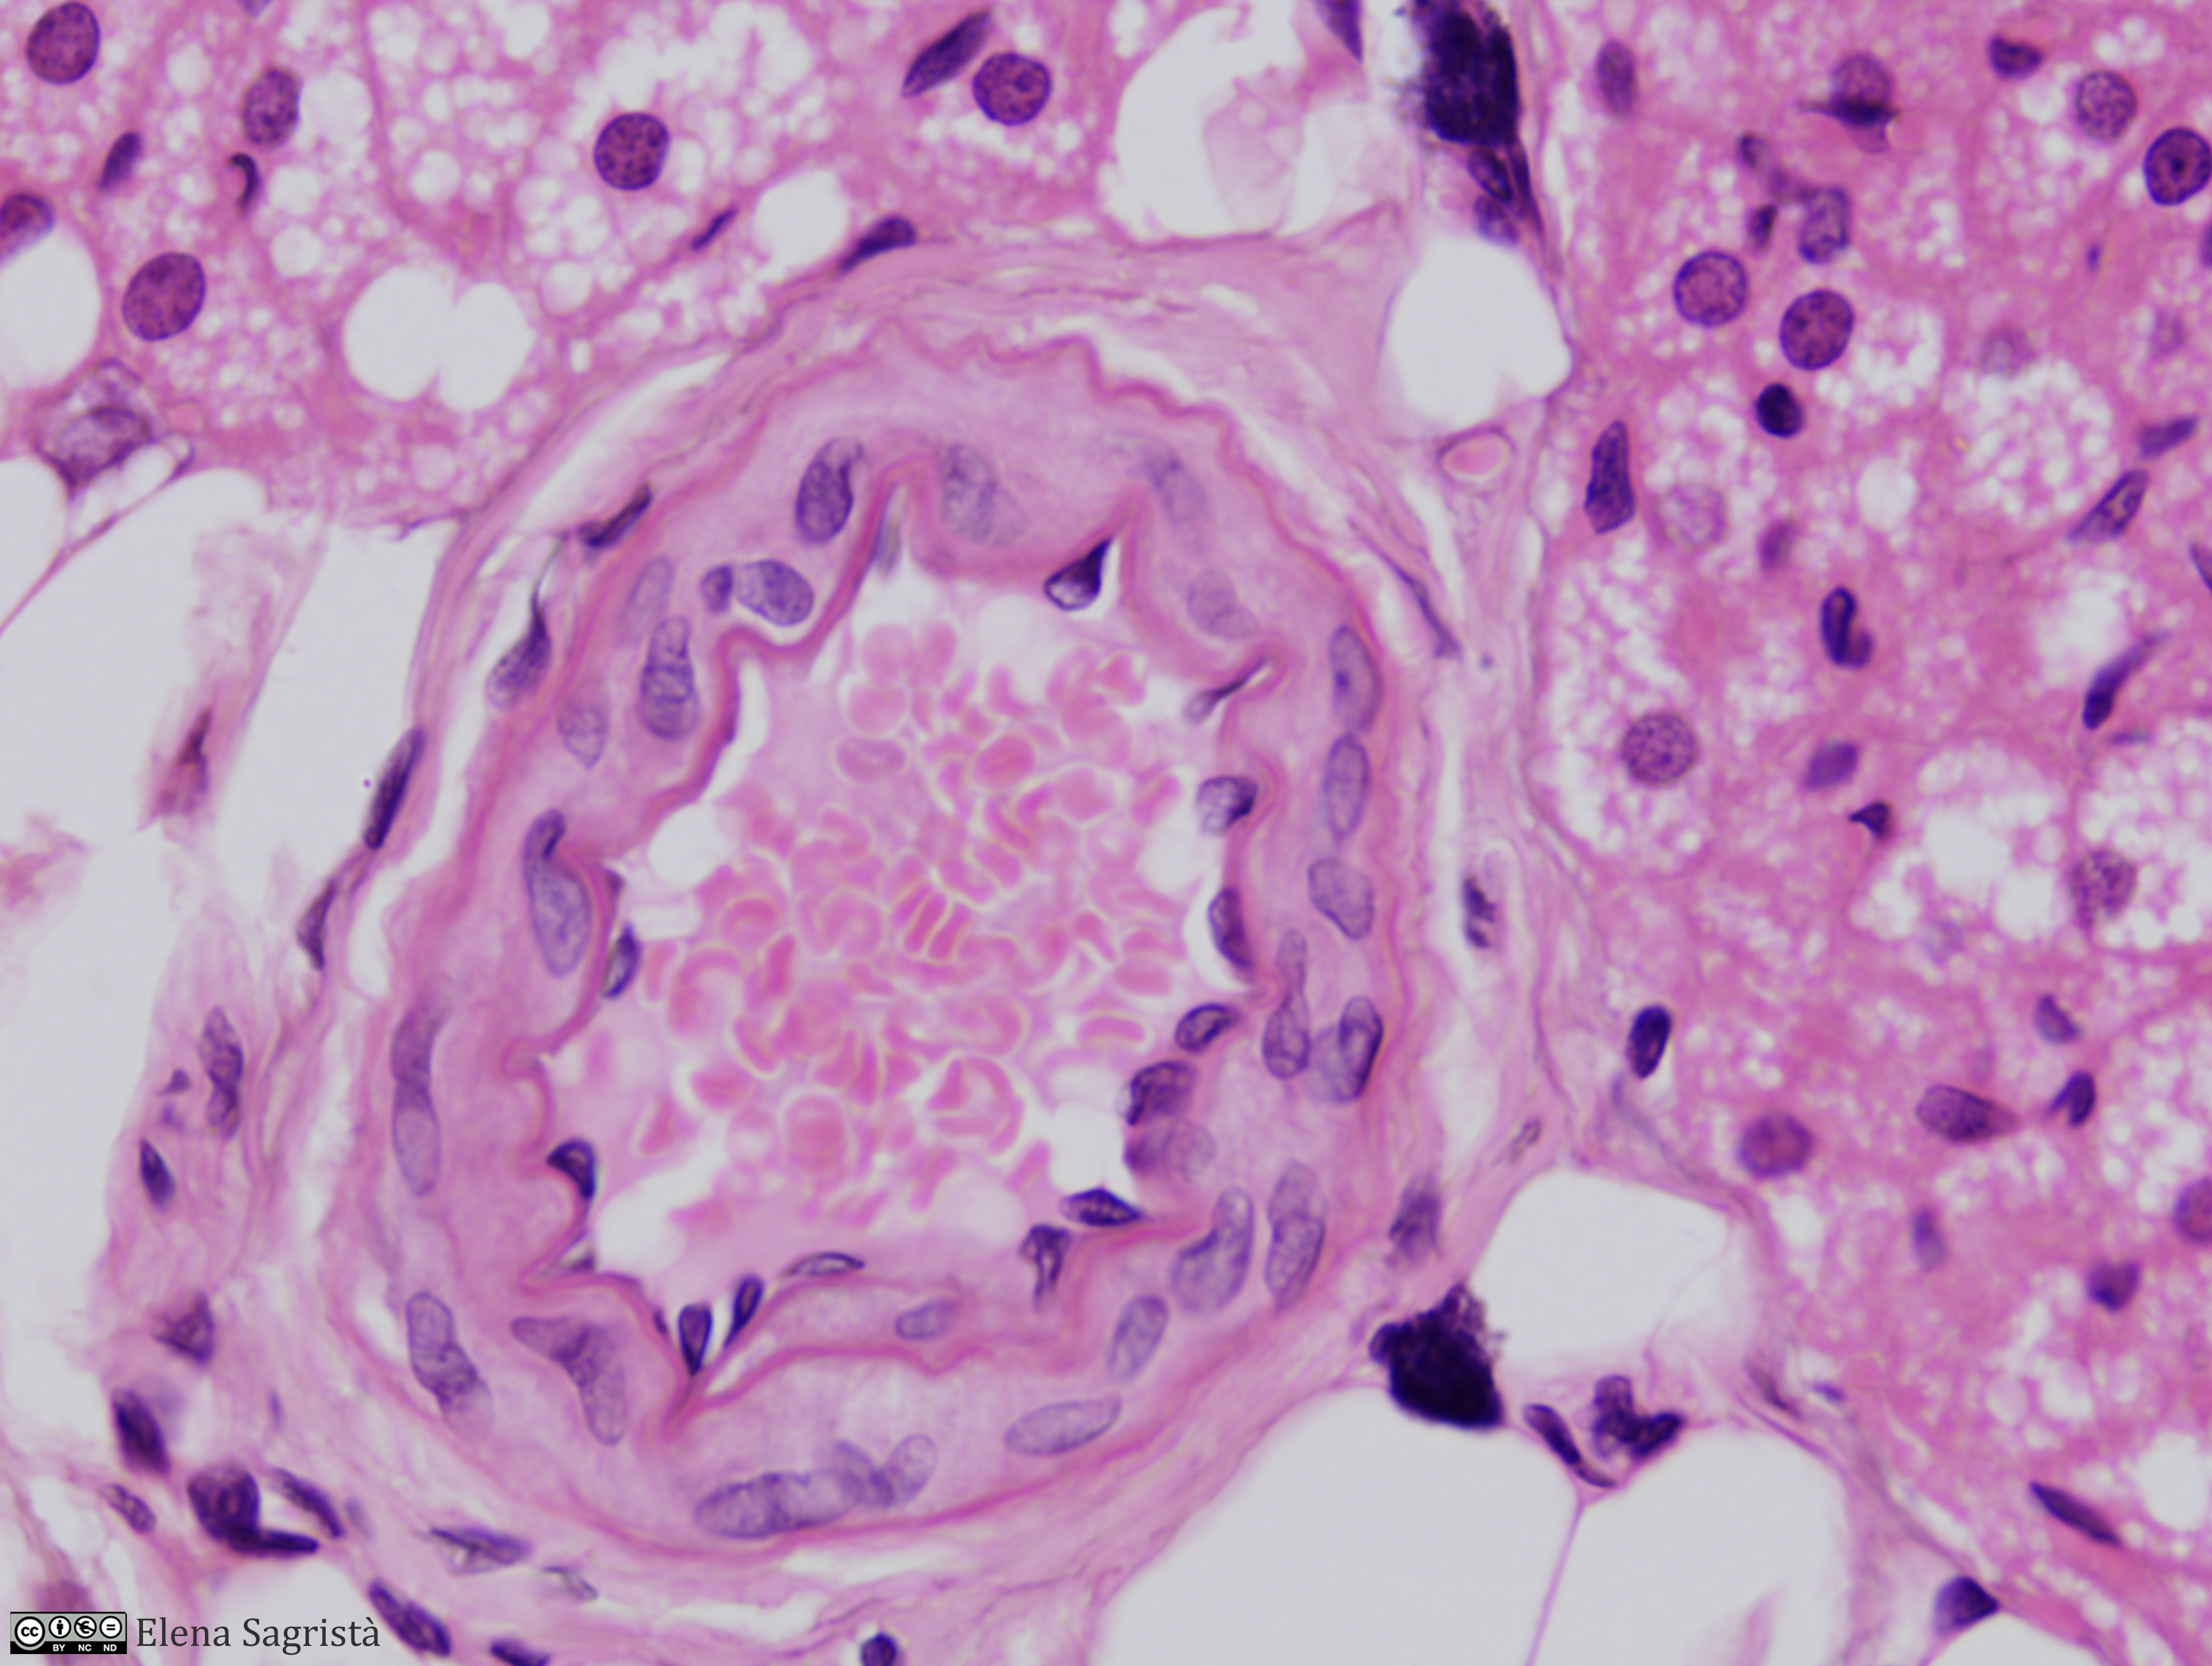

Histologia imatges: 10 Vasos sanguinis i limfàtics

Imatges de preparacions histològiques de Vasos sanguinis i limfàtics. Microscopia òptica.